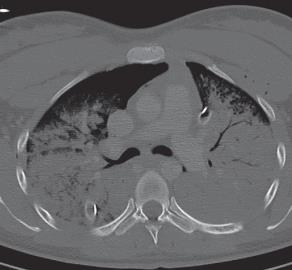

16.2. ábra. Behatoló koponyasérülés CT képe (a szerző felvétele).

A másodlagos robbanásos mechanizmus gyakran eredményezi a testüregek behatoló sérülését, elsősorban a hasüreg és a mellkas érintett.